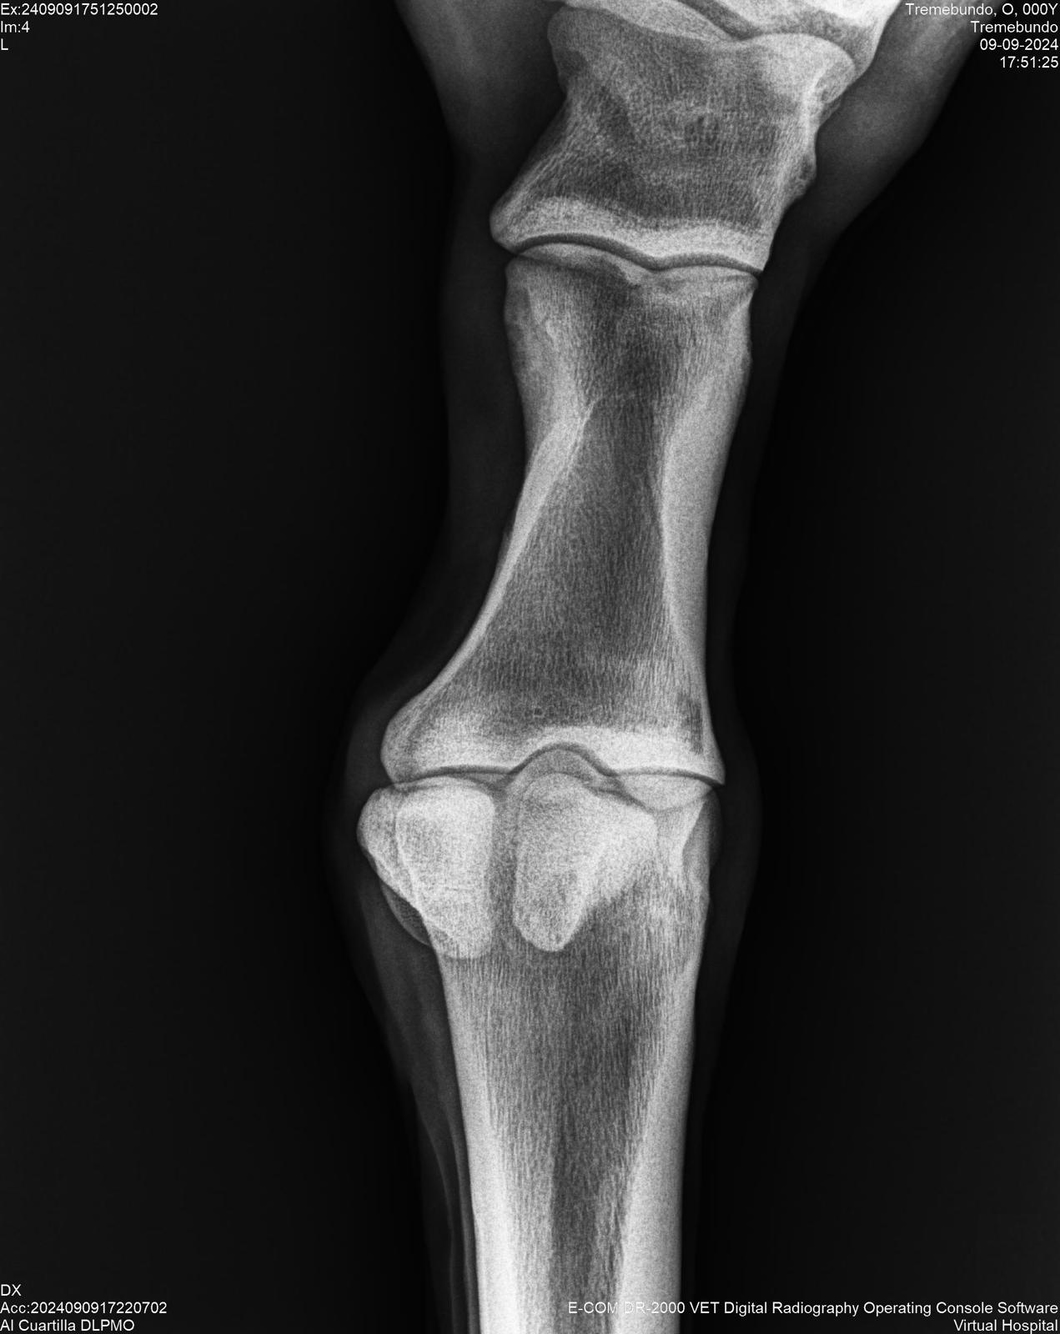

LOTE 37, TREMEBUNDO

Identificador: #291140-

Generacion 2022